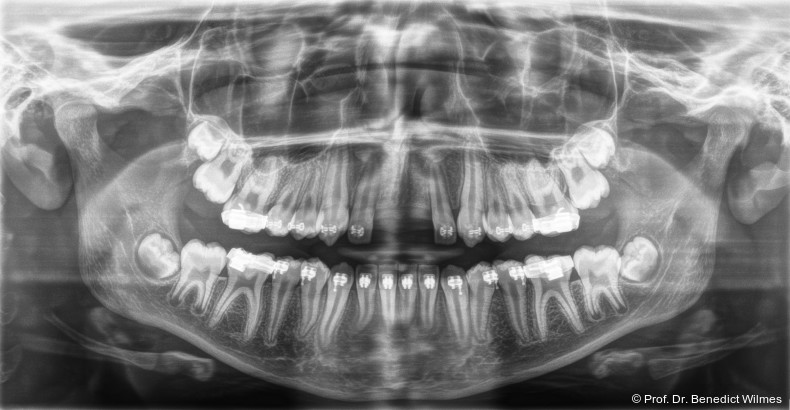

Ein 14-jähriger Patient wurde bei Aplasie der beiden oberen seitlichen Schneidezähne mit dem Ziel der beidseitigen Lückenöffnung kieferorthopädisch therapiert (Abb. 1a+b). Zum Ende der kieferorthopädischen Behandlung wurden zwei Miniimplantate in Regio 2er als temporärer Zahnersatz inseriert (Benefit System, PSM, 2 x 13 mm, Abb. 2a+b). Nach Abdrucknahme wurden Kronen auf den Peek-Abutments modelliert und diese mit Kunststoff auf die Abutments geklebt (Abb. 3a–d). In den Abbildungen 3 und 4 sind die klinischen und röntgenologischen Nachkontrollen innerhalb der nächsten achteinhalb Jahre dokumentiert. Man erkennt einen sowohl in der Höhe als auch in bukkopalatinalen Breite verbleibenden gesunden Knochen ohne Anzeichen einer Atrophie. Im Alter von 23 Jahren wurden die definitiven Implantate ohne die Notwendigkeit einer Augmentation eingesetzt (Abb. 5) und nach Einheilung prothetisch versorgt (Abb. 6a–e und Abb. 7a–c).

Bei einer elfjährigen Patientin fehlten bei Zustand nach Frontzahntrauma im Alter von neun Jahren beide oberen mittleren Schneidezähne (Abb. 8a+b). Als temporärer Ersatz wurden Miniimplantate (Abb. 9, 2 x 13 mm) eingesetzt und Kronen im Labor angefertigt, welche auf den Miniimplantaten verschraubt wurden (Abb. 10a+b). Die Miniimplantate wurden im Alter von 19 Jahren, also nach achtjähriger Nutzung (Abb. 11a+b), durch dentale Implantate ersetzt.

Nach Abschluss der kieferorthopädischen Pfeilerverteilung wurden zwei Miniimplantate in Regio 3er inseriert (2 x 13 mm). Nach Herstellung im Labor wurden Kronen auf den Miniimplantaten aufgeschraubt (Abb. 13+16a–d). Auch hier wurde darauf geachtet, dass die Kronen aus der Okklusion geschliffen wurden (Abb. 14). Bei den Nachkontrollen zeigten sich ebenfalls stabile Miniimplantate und ein entzündungsfreies Implantatlager ohne erkennbare Atrophie des Knochens (Abb. 15 und 16a–d).